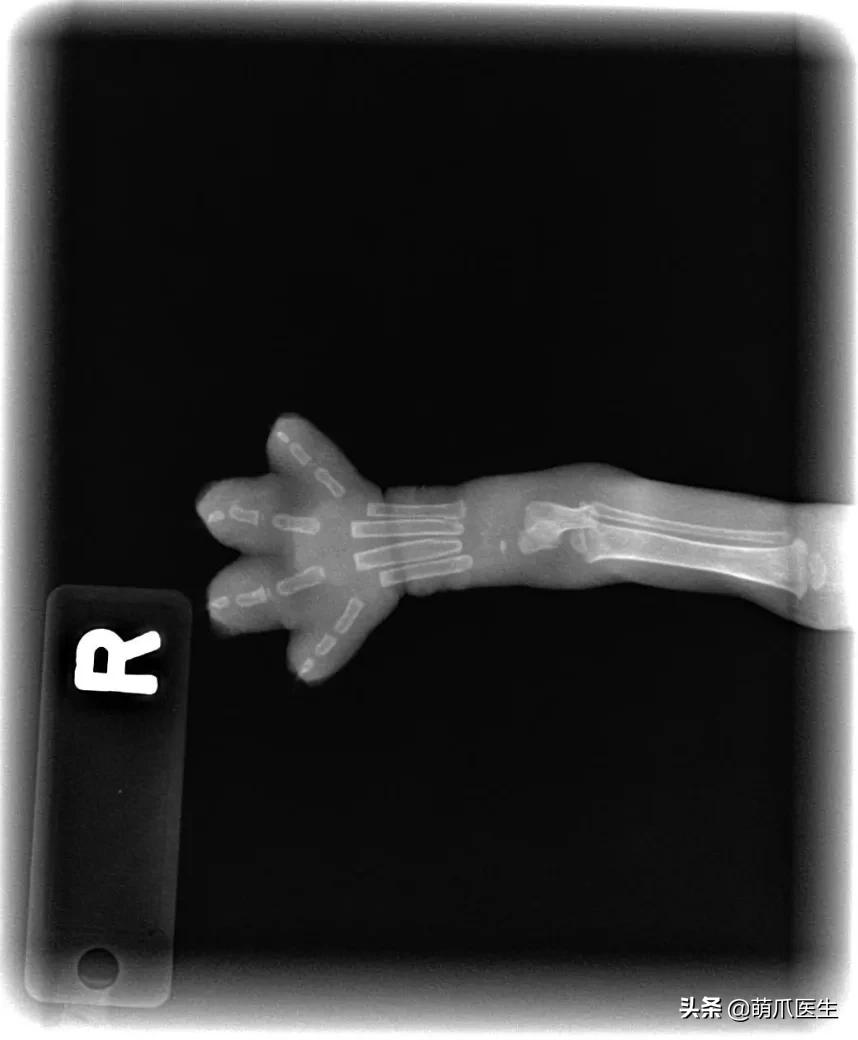

为了证明自己没有作假,LinzerBinzer不得不上传了小猫咪另一只脚的X光片,看上去确实是同样的效果……

另一部分支持LinzerBinzer的网友则帮他解释说:

小猫年龄只有5~6周大,骨骼系统还没有完全发育。此时它骨头之间相连的结缔组织在X射线下是透明的,所以看上去才会如此“不真实”。